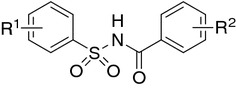

Fig. 1.

Fig. 2.

Acyl sulfonamide antiproliferative (ASAP) scaffold [26]

Fig. 3.

Tasisulam sodium (LY573636-sodium): clinically evaluated (phase II/III in metastatic melanoma) antitumor N-acylsulfonamide; pan-Bcl family inhibitors targeting Bcl-2, Bcl-w, and Bcl-xL: WO-2002024636, ABT-737, and ABT-263 [23–25]